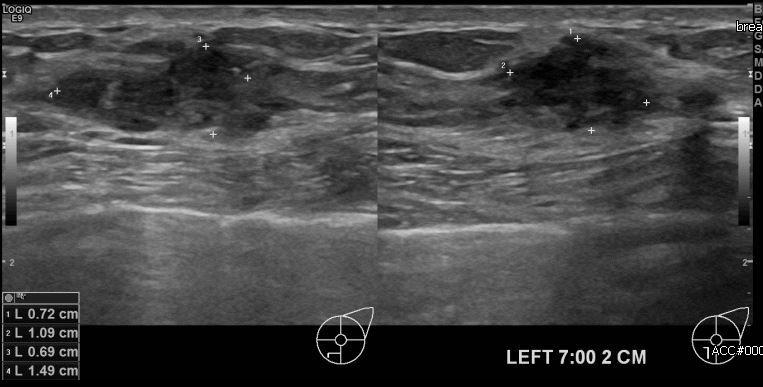

상기환자 건강검진상 이상소견으로 내원하신 40대 여성분으로 좌측 7시 방향에서

2cm 떨어진 거리에 의심스러운 멍울 조직검사 시행하여 좌측 유두암 진단 되었습니다.